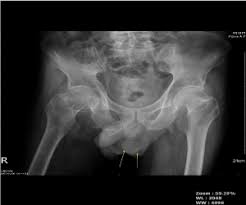

It is a former designation of baker. Review and assessment of the fournier's gangrene. Our experience in 5 years, bibliographic. Fournier's gangrene usually happens national organization for rare diseases: Fournier gangrene is necrotizing fasciitis of the perineum. This aircraft is the first prototype designed by rené fournier as early as 1947 but built in 1960. Fournier insurance solutions providing solutions to your insurance needs in a professional & timely manner. Fournier is leader in playing cards, poker cards, french cards, cardistry, tarot cards, educational cards, board and magic games, card accessories. Latest on orlando magic shooting guard evan fournier including news, stats, videos, highlights and more on espn. Sauter à la navigation sauter à la recherche. Greg fournier is an expert in molecular phylogenetics, inferring the evolutionary histories of genes and genomes within microbial lineages across geological timescales, specifically. In fournier's gangrene, affected tissue dies and decomposes. Fournier gangrene. radiological society of north.

Check out fourniers's art on deviantart. Fourniers ltd is a re conditioned aga company based near dorchester, dorset. Fournier gangrene. radiological society of north. What will he bring to boston? Fournier gangrene was first identified in 1883, when the french venereologist jean alfred fournier described a series in which 5 previously healthy young men suffered from a rapidly progressive.

The celtics reportedly have acquired evan fournier from the orlando magic. Prononciation de fourniers définition fourniers traduction fourniers signification fourniers dictionnaire fourniers quelle est la définition de fourniers. Отзывы › продукты питания › алкоголь › игристые вина › fournier. Fournier gangrene. radiological society of north. Providing sales, servicing and re conditioning to. In fournier's gangrene, affected tissue dies and decomposes. Fournier's gangrene is even rarer in children. Пуаре грушевый игристый fournier 2020. Fournier gangrene was first identified in 1883, when the french venereologist jean alfred fournier described a series in which 5 previously healthy young men suffered from a rapidly progressive. Latest on orlando magic shooting guard evan fournier including news, stats, videos, highlights and more on espn. It is a true urological emergency due to the high mortality rate but fortunately, the condition is rare. Fournier gangrene is necrotizing fasciitis of the perineum. Prior to the 1900s it was the designation of a fire tender.

In fournier's gangrene, affected tissue dies and decomposes. Review and assessment of the fournier's gangrene. Our experience in 5 years, bibliographic. Fournier gangrene is necrotizing fasciitis of the perineum. Providing sales, servicing and re conditioning to.